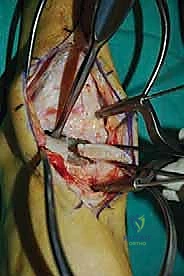

الغوص العميق في جراحة الطعم الخيفي الهيكلي (Structural Allograft Reconstruction)

يهدف هذا الإجراء العبقري إلى استبدال الغضروف والعظم التالفين والميتين بنسيج سليم تماماً مأخوذ من متبرع متوفى (طعم خيفي - Allograft). هذا الطعم يتم تعقيمه وحفظه في بنوك الأنسجة العالمية وفقاً لأعلى المعايير الطبية الصارمة لضمان خلوه من أي أمراض معدية والحفاظ على حيوية الخلايا الغضروفية.

- الترميم التشريحي الحقيقي: يسمح باستعادة الشكل الهندسي الدقيق لعظم الكاحل، بما في ذلك المنحنيات المعقدة لكتف التالوس.

- توفير غضروف طبيعي (Hyaline Cartilage): الغضروف المزروع هو غضروف زجاجي طبيعي،